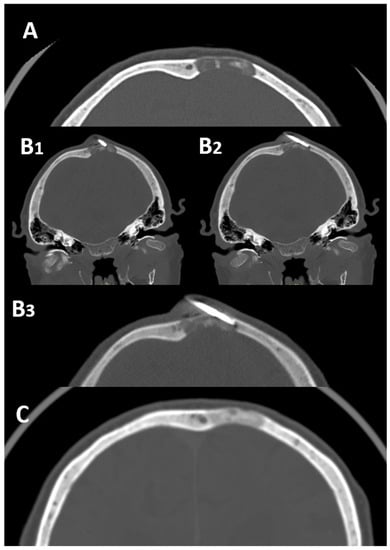

2.1. Skull